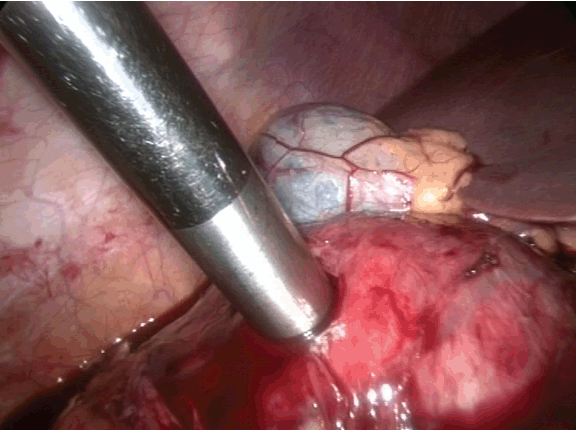

On the operation table laparoscopy showed cystic mass. (Figure 2) With preoperative diagnosis of hydatid cyst, aspiration revealed straw colour fluid at the beginning with cheesy material with hydatid cannula. (Figure 3) Deroofing of the cyst was done. (Figure 4) Later frank blood started coming which could not be controlled, (Figure 5) so abdomen was opened by right sub costal incision. Whole of the cyst cannot be removed since its close proximity to inferior vena cava and duodenum, however, most of the cyst wall was removed. Hemostasis achieved by placing a ribbon pack which was removed three days postoperatively. Postoperative period was uneventful.

Figure 3: Suction of contents of the cyst using hydatid cannula.